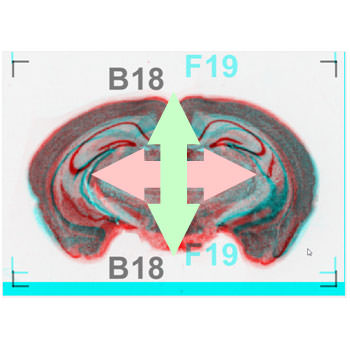

スライス画像(連続切片/医用画像/FIB-SEM/SBF-SEM)位置合わせ

概要

• 一括画像処理

• スライス画像(連続切片/医用画像/FIB-SEM/SBF-SEM)位置合わせ

対応データ

• FIB-SEMの計測データ(BMP/TIFF/JPG等)

納品データ

• 位置合わせ画像(BMP/TIFF)

• ご報告書